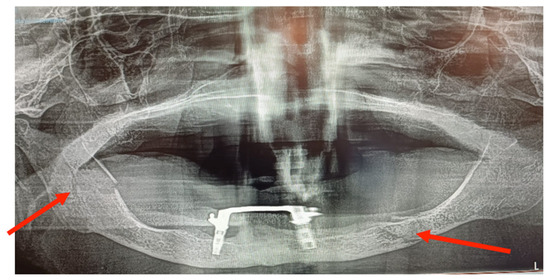

3.2. Case 2